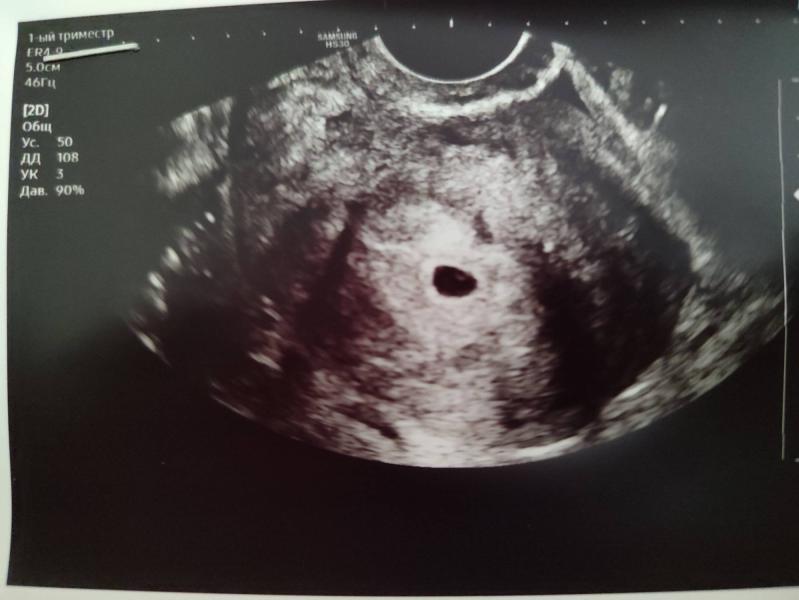

Видео ли на фото желточный мешок? Или плка просто ПЯ видно?

Девочки в 5.1 жм 4мм а эмбриона не видно. Это нормально?